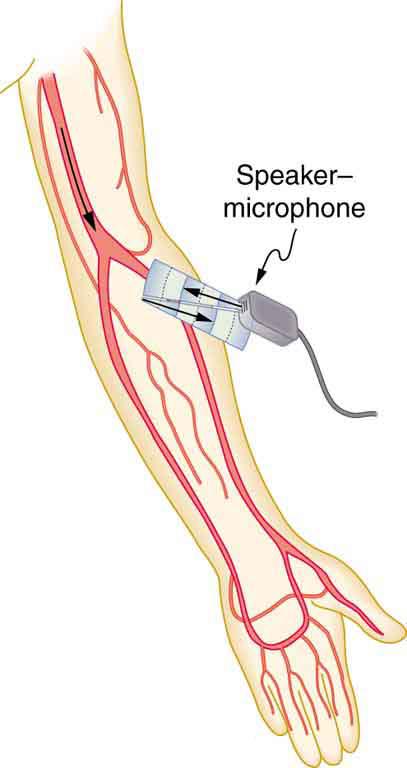

Another major use of ultrasound in medical diagnostics is to detect motion and determine velocity through the Doppler shift of an echo, known as Doppler-shifted ultrasound. This technique is used to monitor fetal heartbeat, measure blood velocity, and detect occlusions in blood vessels, for example. (See Figure 17.49.) The magnitude of the Doppler shift in an echo is directly proportional to the velocity of whatever reflects the sound. Because an echo is involved, there is actually a double shift. The first occurs because the reflector (say a fetal heart) is a moving observer and receives a Doppler-shifted frequency. The reflector then acts as a moving source, producing a second Doppler shift.

A clever technique is used to measure the Doppler shift in an echo. The frequency of the echoed sound is superimposed on the broadcast frequency, producing beats. The beat frequency is and so it is directly proportional to the Doppler shift () and, hence, the reflector’s velocity. The advantage in this technique is that the Doppler shift is small because the reflector’s velocity is small, so that great accuracy would be needed to measure the shift directly. But measuring the beat frequency is easy, and it is not affected if the broadcast frequency varies somewhat. Furthermore, the beat frequency is in the audible range and can be amplified for audio feedback to the medical observer.

Ultrasound that has a frequency of 2.50 MHz is sent toward blood in an artery that is moving toward the source at 20 cm/s, as illustrated in Figure 17.50. Use the speed of sound in human tissue as 1,540 m/s. Assume that the frequency of 2.50 MHz is accurate to seven significant figures.